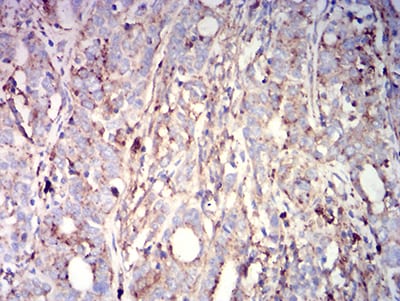

分类: 科研抗体货号: 31410别名: APCL应用: IHC,IF,FCM反应种属: Human

分类: 科研抗体货号: 31424别名: MLA1; ME491; LAMP-3; OMA81H; TSPAN30应用: IHC,FCM反应种属: Human

分类: 科研抗体货号: 31423别名: MLA1; ME491; LAMP-3; OMA81H; TSPAN30应用: IHC,FCM反应种属: Human